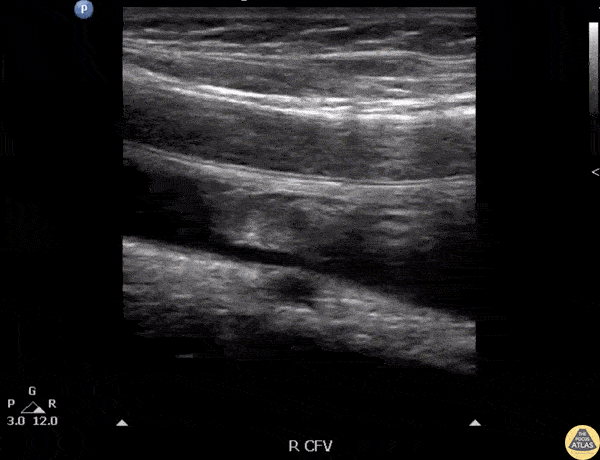

POCUS revealed an acute DVT becoming easily mobile when the patient coughs. Image courtesy of Robert Jones DO, FACEP @RJonesSonoEM Director, Emergency Ultrasound; MetroHealth Medical Center; Professor, Case Western Reserve Medical School, Cleveland, OH View his original post here